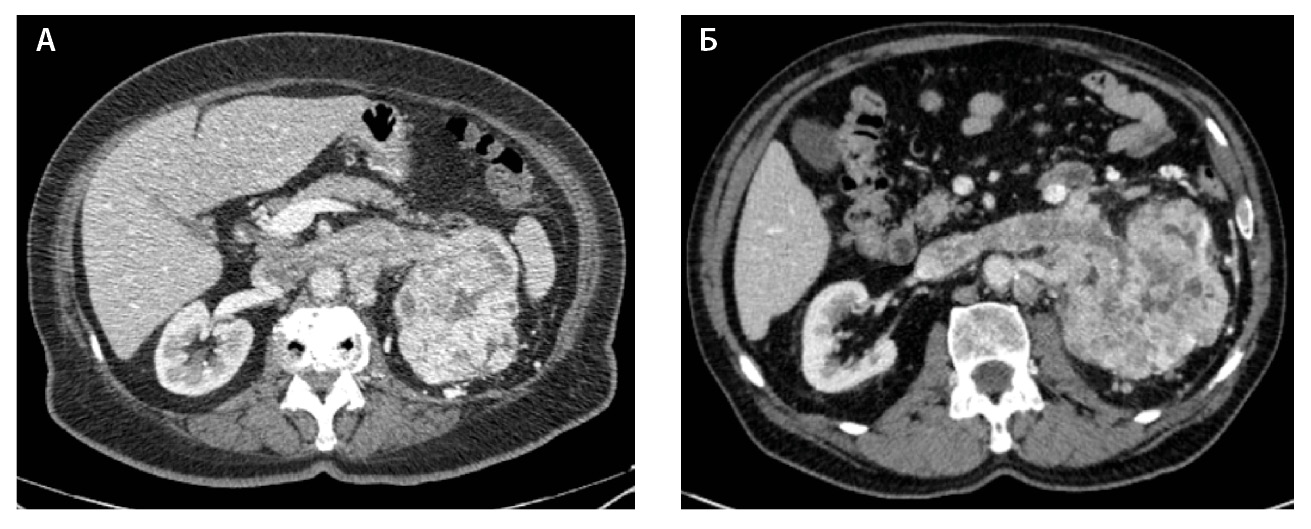

Компьютерная томография (КТ) с внутривенным контрастным усилением широко используется как метод диагностики и первичного стадирования скПКР. В настоящее время наиболее значимыми характеристиками опухоли для предоперационного стадирования и планирования хирургического лечения скПКР признаны расположение, размер опухоли и признаки ее инвазивного роста [3–6], а структура и характер контрастирования позволяют дифференцировать типы ПКР, но ни один из этих показателей не дает возможности достоверно прогнозировать степень дифференцировки опухоли. Структура скПКР любой степени дифференцировки, как правило, гетерогенная с наличием солидного и кистозного компонентов. Признаки инвазивного роста опухоли, наличие метастазов позволяют предположить низкую степень дифференцировки опухоли, однако не являются достоверными признаками. Как видно на рис. 1, скПКР разной степени дифференцировки по данным КТ выглядят практически идентично: в обоих случаях визуализируется опухолевый тромб в почечной вене с распространением в просвет нижней полой вены. Такие характеристики, как размер опухоли, пофазное накопление контрастного вещества и градиент накопления контрастного вещества при КТ-исследовании, также не являются строго специфичными для разных степеней дифференцировки скПКР (рис. 2).

Рис. 1. Светлоклеточный почечно-клеточный рак: А – Grade 4 (данные компьютерной томографии пациентки Б.), Б – Grade 2 (данные компьютерной томографии пациента Г.). На обоих снимках кортико-медуллярная фаза исследования: гиперваскулярная опухоль солидно-кистозного строения, замещающая паренхиму левой почки, опухолевый тромб в просвете левой почечной вены с распространением в нижнюю полую вену; метастически измененный регионарный лимфатический узел

Рис. 2. Светлоклеточный почечно-клеточный рак. А – Grade 1 (данные компьютерной томографии пациента С.), кортико-медуллярная фаза исследования: трансмуральная опухоль правой почки размером 6,6 см, с четкими и ровными контурами, прилежит к синусу почки, опухоль имеет солидно-кистозное строение, солидный компонент опухоли накапливает контрастное вещество (КВ) менее интенсивно, чем кортикальный слой почки, градиент накопления КВ солидным компонентом опухоли 50–60 HU. Б – Grade 4 (данные компьютерной томографии пациентки Щ.), кортико-медуллярная фаза исследования: трансмуральная опухоль левой почки размером 5,2 см, с четкими и ровными контурами, прилежит к синусу почки, опухоль имеет солидно-кистозное строение, солидный компонент опухоли накапливает КВ менее интенсивно, чем кортикальный слой почки, градиент накопления КВ солидным компонентом опухоли 45–60 HU